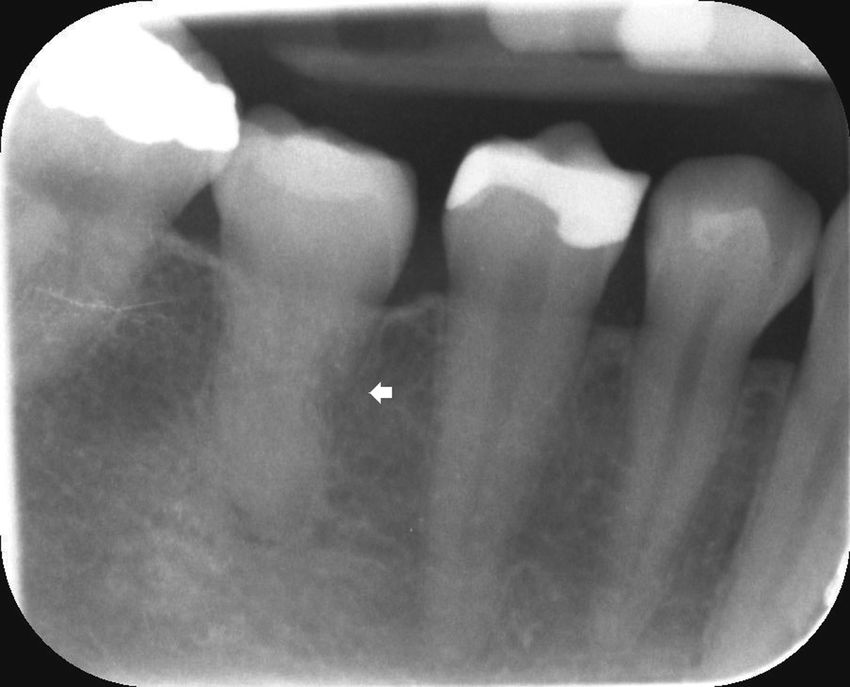

- Un élargissement de l’espace desmodontal évoque une surcharge occlusale, un traumatisme ou une parodontite apicale

Pourquoi c’est problématique : Un élargissement de l’espace desmodontal invisible cliniquement peut être la première signature radiographique d’une surcharge occlusale, d’une parodontite apicale débutante ou d’un kyste périapical.

Prise en charge : Le bilan parodontal (sondage, radiographies rétroalvéolaires) révèle une poche de 6 mm en mésial de 21, avec une lyse osseuse angulaire à la radio. L’espace desmodontal est élargi, témoignant d’une mobilité pathologique liée à la perte de support osseux.

Point clé illustré : L’élargissement de l’espace desmodontal en radiographie est un marqueur objectif de la surcharge mécanique liée à la perte de support. Le tabac aggrave la progression des parodontites en perturbant le turn-over du desmodonte et la réponse immunitaire.

4. Quelle est la signification clinique d’un élargissement de l’espace desmodontal à la radiographie ?

Un élargissement peut signer plusieurs situations : une surcharge occlusale (trauma occlusal), une parodontite apicale évolutive, un abcès desmodontal, une tumeur, ou une fracture radiculaire. Il faut toujours corréler avec la clinique (sondage, percussion, test de vitalité) pour orienter le diagnostic.